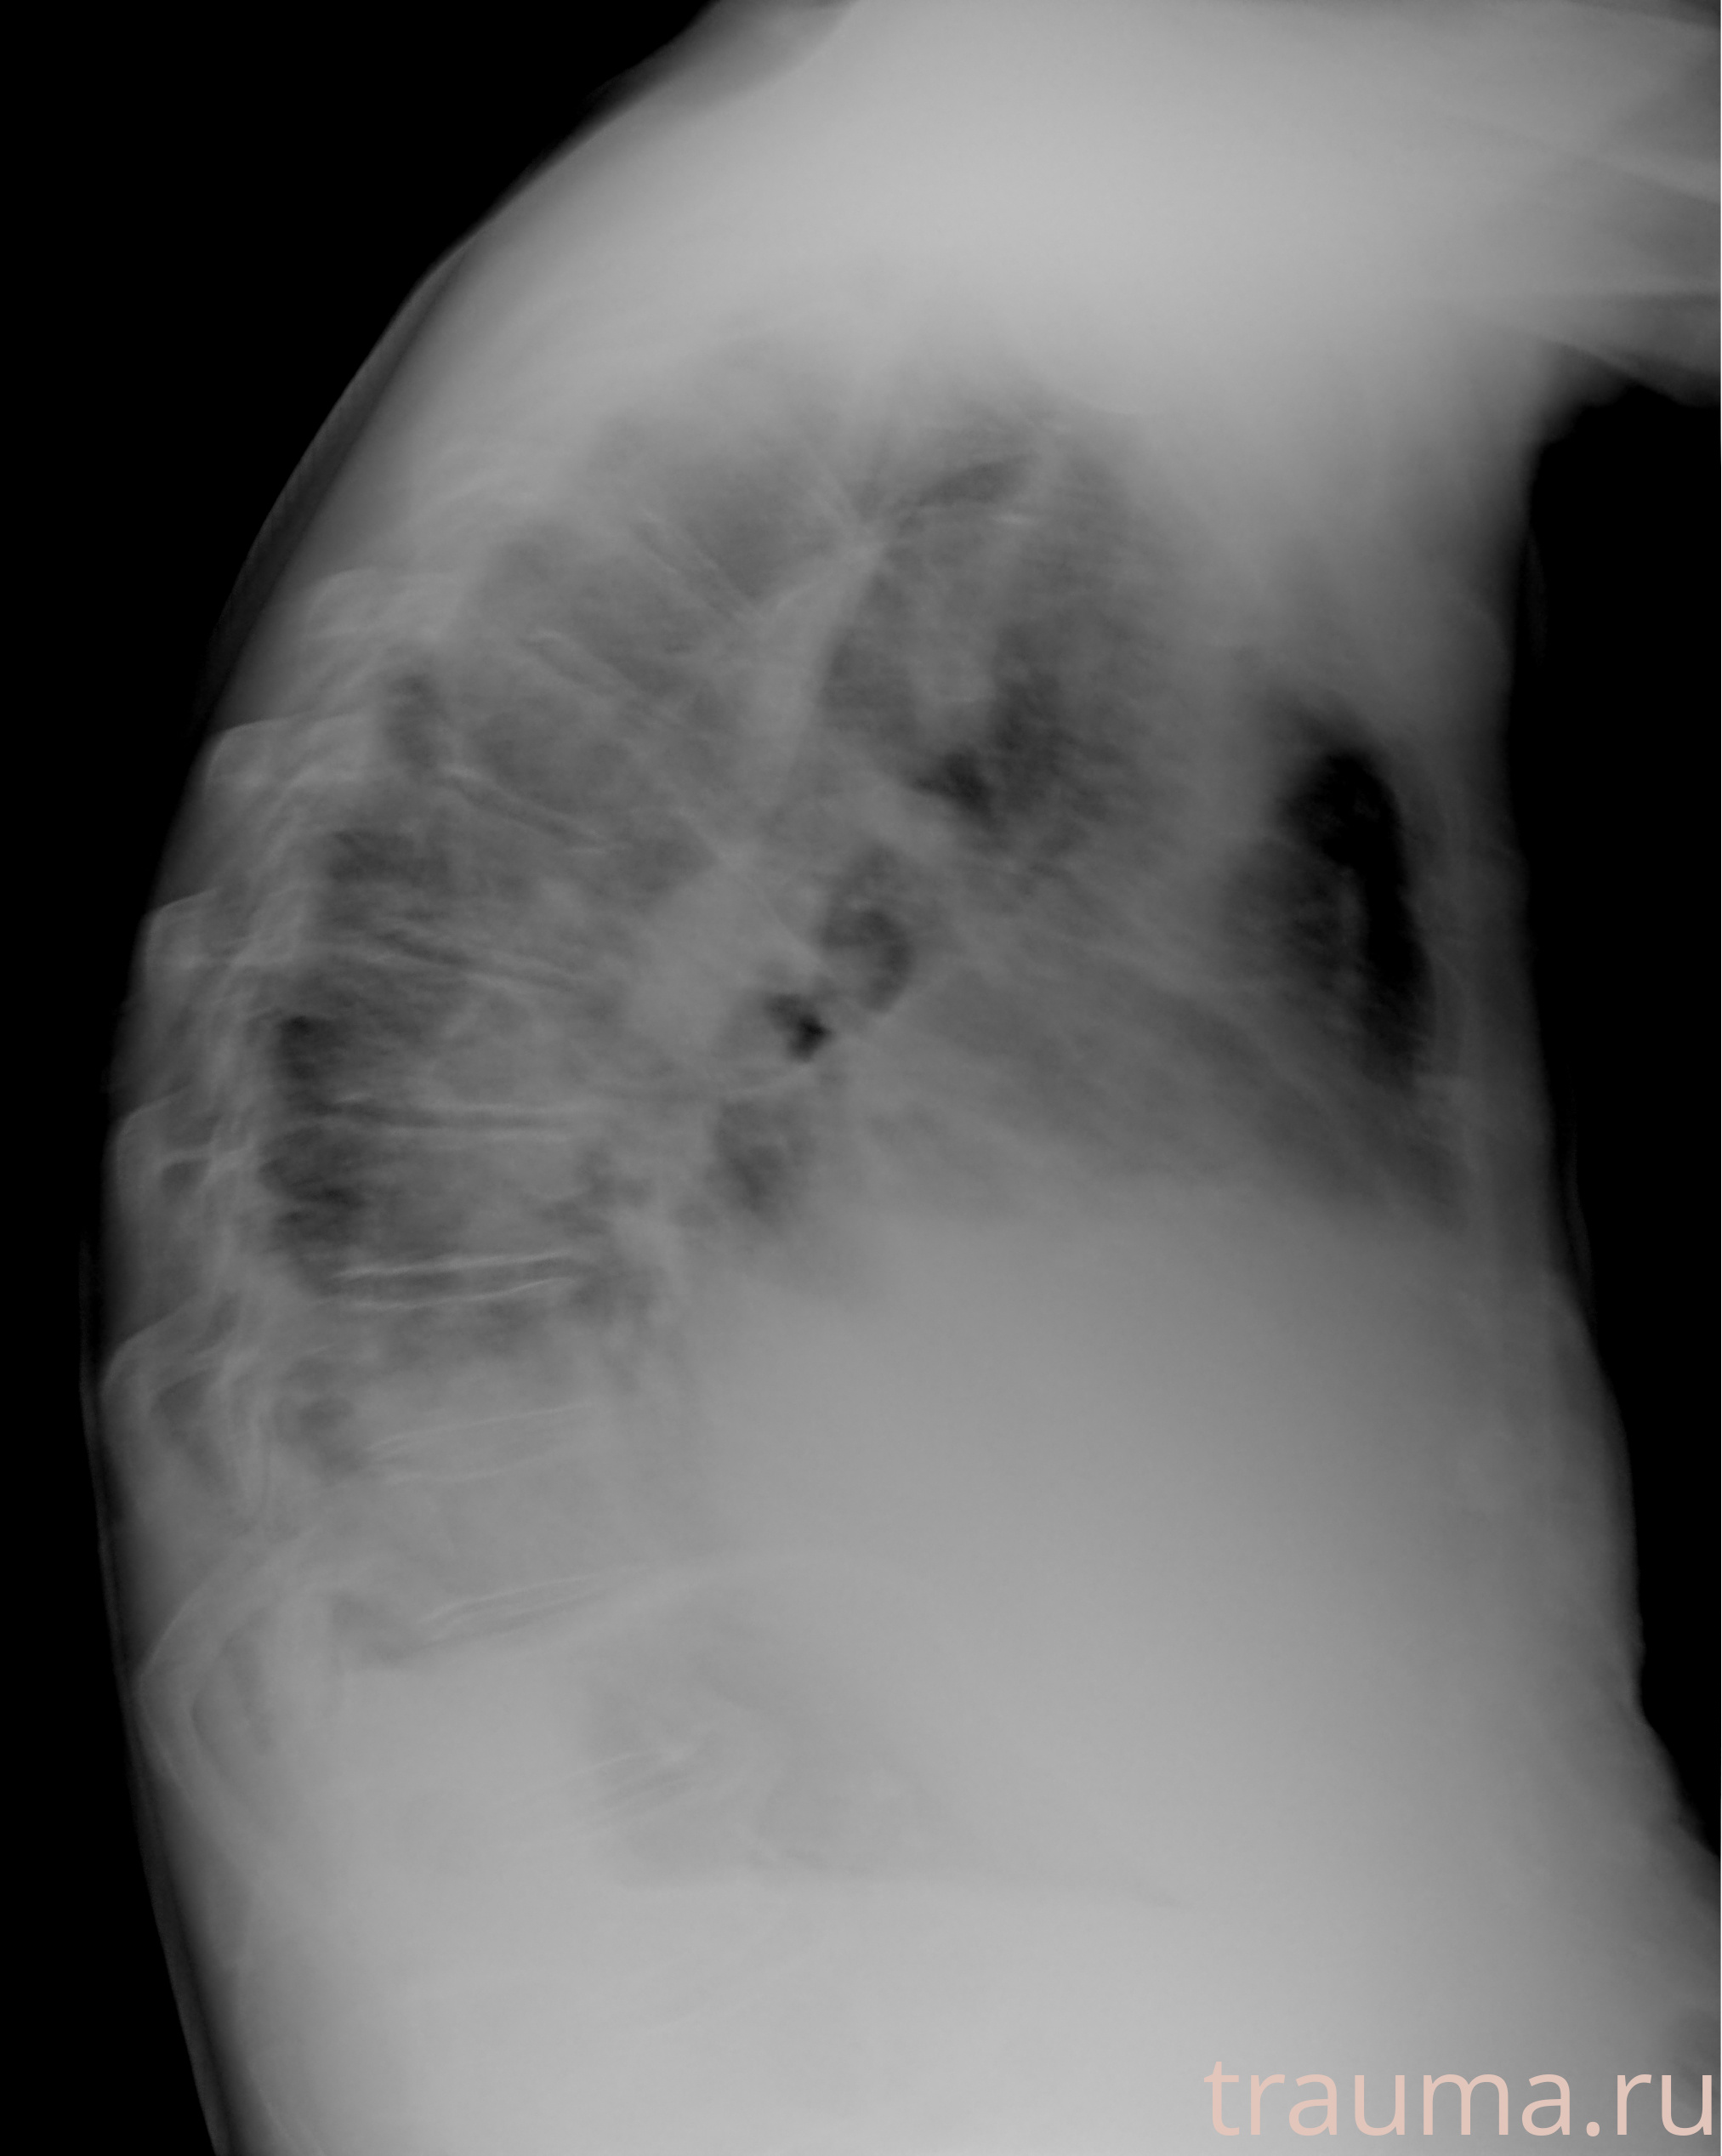

Рентгенограммы

Рентген на дому: по вашему адресу приезжает врач-рентгенолог, травматолог-ортопед с мобильным рентгеновским аппаратом, проводит диагностику травмы или заболевания, делает необходимые рентгенограммы, дает рекомендации по дальнейшему лечению. Получить качественные снимки в домашних условиях возможно благодаря уникальной методике, разработанной МосРентген Центром для института  Склифосовского

при переломе шейки бедра и пневмонии от компании МосРентген Центр - партнера Института имени Склифосовского